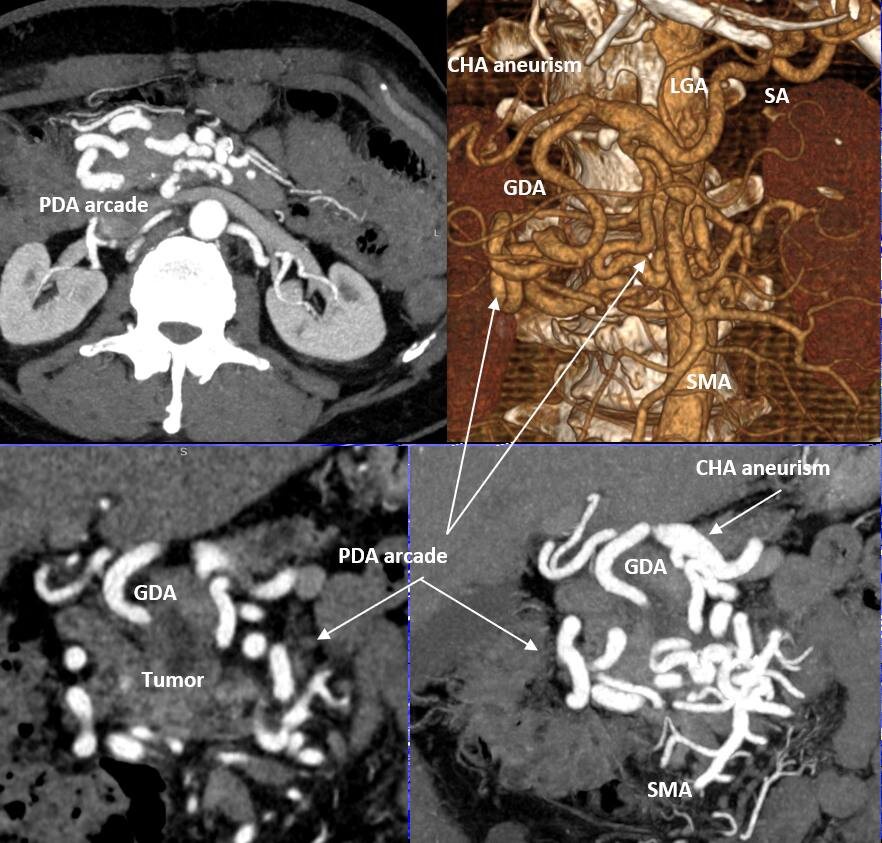

Панкреатодуоденальная резекция (ПДР) с транспозицией чревного ствола (ЧС) в правую общую подвздошную артерию и резекцией c протезированием общей печеночной артерии (ОПА) по поводу местнораспространенной протоковой аденокарциномы головки поджелудочной железы (ПЖ) с вовлечением гастродуоденальной артерии (ГДА) на фоне нестентируемого стеноза ЧС и аневризмы ОПА. Панкреатодуоденальная аркада (ПДА) и ГДА в данном случае  – основной источник кровоснабжения печени, желудка, 12-перстной кишки, поджелудочной железы и селезенки.

R0-PANCRETODUODENECTOMY ASSOCIATED WITH CELIAC TRUNK (CT) TRANSPOSITION INTO THE RIGHT COMMON ILIAC ARTERY AND COMMON HEPATIC ARTERY (CHA) RESECTION AND PROSTHETICS FOR LOCALLY ADVANCED PANCREATIC CANCER on the background of non-stentable long-lasting СT stenosis and CHA aneurism. Gastroduodenal artery (GDA) and pancreaicodudenal arcade in this case were the main sources of blood supply for the liver, pancreas, spleen, stomach and duodenum. ypT4N0 (48/0) M0

Месяц назад мы выписали домой пациента после вышеуказанной операции. У крепкого, 60-летнего мужчины за несколько месяцев до этого был обнаружен рак головки ПЖ. Важной особенностью было то, что также был выявлен протяженный и выраженный стеноз (сужение) чревного ствола (ЧС), одной из двух крупных артерий, снабжающих практически все органы брюшной полости. Это сужение было обусловлено (видимо, с рождения) давлением дугообразной связки диафрагмы на ЧС сразу после его отхождения от аорты. О том, что это сдавление было очень длительным, говорило то, что коллатеральные артерии (дополнительные сосуды, неработающие в норме и поэтому имеющие малый диаметр), которые обычно не видны на КТ, достигли диаметра, равного нормальному диаметру основных висцеральных артерий – ЧС и верхней брыжеечной артерии (ВБА). В нашем случае ЧС был представлен тонюсеньким сосудом, а коллатерали шли от ВБА и снабжали артериальной кровью печень, желудок, 12-перстную кишку, поджелудочную железу и селезенку. Коллатерали проходили через головку поджелудочной железы, опухоль которой вросла в эти сосуды, от которых зависело кровоснабжение жизненно важных органов (см. фото), и за счет этого опухоль перешла из разряда резектабельных в разряд местнораспространенных. Мало того, длительные нарушения гемодинамики привели к образованию аневризмы (патологического расширения) общей печеночной артерии (ОПА) – ключевого сосуда, через который снабжались в нашем случае не только печень, но и остальные ранее перечисленные органы.